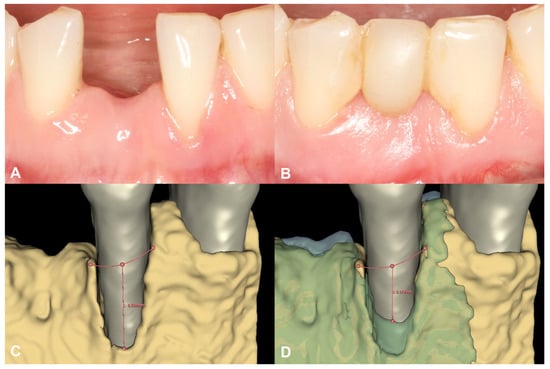

3.1. Case #1

3.1.1. Baseline Clinical Situation

3.1.2. Short-Term Hard Tissue Gain and Two-Year Follow-Up

3.2. Case #2

3.2.1. Baseline Clinical Situation

3.2.2. Short-Term Volumetric Hard Tissue Gain and Long-Term Follow-Up